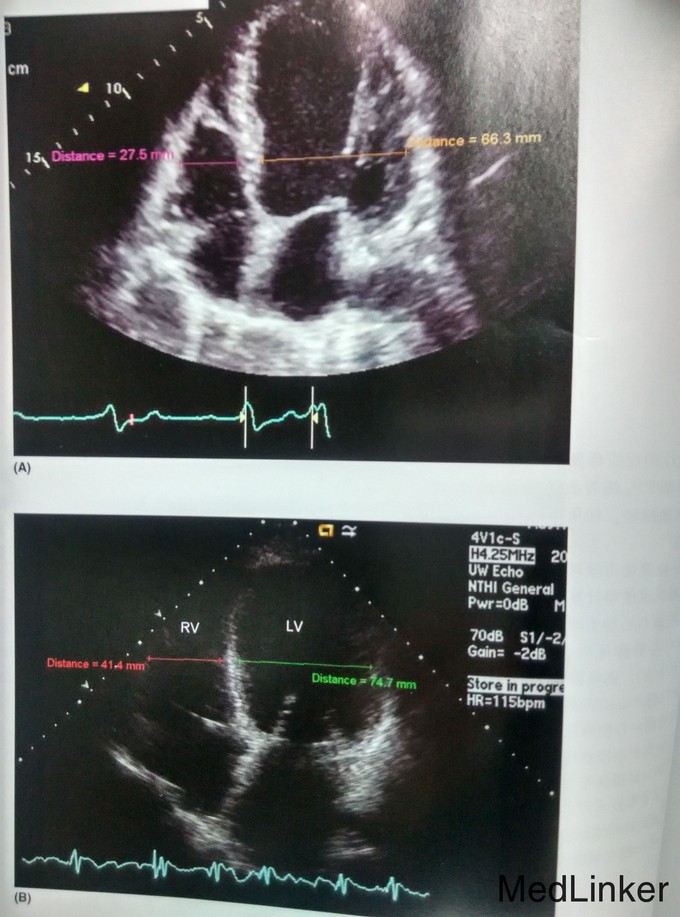

患者目前感觉运动耐量恢复到发病前的状态,能全天工作,但超声心动图显示射血分数只有10-20%的轻度恢复,左心室仍然扩大成球形。规律使用螺内酯25mg。 讨论:超声心动图可以提供哪些信息 1.跟左心室功能有关的指标。 2.左心室大小。 3.关于右心室的大小和功能, 4.关于心房的功能和大小。